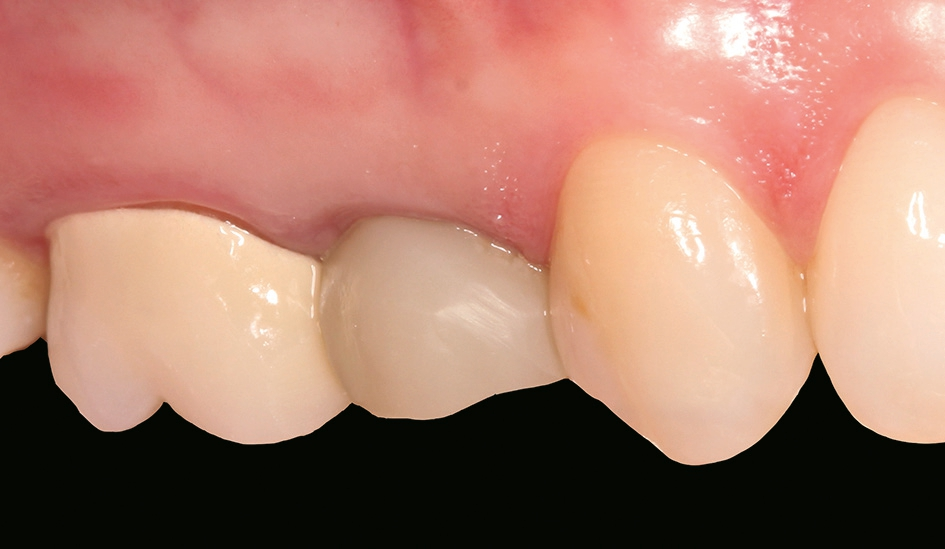

Nach einer komplikationsfreien Einheilzeit von vier Monaten konnte mit der Herstellung des definitiven Zahnersatzes begonnen werden. Hier entschied man sich konsequent für monolithische Kronen aus Lithiumdisilikat, um das Chippingrisiko so gering wie möglich zu halten [12]. Im Zuge der Implantatversorgung wurde nun auch – wie geplant – die metallkeramische Krone an 16 geschlitzt, entfernt und der Stumpf nachpräpariert. Implantatkopf und Zahnstumpf wurden daraufhin zusammen mit A-Silikon analog abgeformt. Für die geschlossene Abformung wurde die Abformkappe (impression.transfer) auf dem Implantatkopf positioniert. Ein deutliches Einrasten signalisierte den lagestabilen Sitz. Für die Modellherstellung rastete das Implantatanalog (lab. replica) ebenso in die integrierte Abformkappe ein. Nach der Herstellung des Meistermodells konnten die beiden Kronen im digitalen Workflow CAD/ CAM-gestützt gefertigt werden. Nach Ausarbeitung, Bemalung und Glasur waren die beiden Kronen für die definitive Zementierung bereit. Die klinische Einprobe der Restaurationen verlief erfolgreich, sodass die Kronen nacheinander mit selbstadhäsivem Befestigungskomposit eingegliedert werden konnten.

Auch wenn die Sofortimplantation mit dem ceramic.implant nicht Teil des offiziellen Indikationsspektrums ist, erwies sich das einteilige keramische Implantat wie schon mehrfach in anderen dokumentierten Fällen als schnelle, ästhetische und sichere Versorgungsform. Natürlich müssen alle Grundvoraussetzungen für eine Sofortimplantation gegeben sein. Eine penible Risikoanalyse sollte deswegen im Vorfeld immer durchgeführt werden. Das Implantationsgebiet muss entzündungsfrei, genügend Knochen in der Schaltlücke vorhanden und eine gute Mundhygiene sowie Compliance von Patientinnen und Patienten gegeben sein. Ein dicker Gingivatyp erhöht signifikant die Wahrscheinlichkeit für stabile gingivale Verhältnisse [13]. Aber auch Allgemeinerkrankungen und die etwaige Einnahme von Medikamenten entscheiden darüber, ob eine Sofortimplantation vertretbar ist oder nicht [14,15]. Im Zweifelsfall sollte die Entscheidung auf eine geschlossene Einheilung fallen.

Die Einteiligkeit macht zwar ein Mehr an Planung notwendig, die Spaltfreiheit bietet aber gerade bei der offenen Einheilung eine Infektionsprävention. Im Zusammenspiel mit der Gewebsverträglichkeit von Zirkondioxid führte dies zu einer komplikationsfreien Einheilung. Gerade im Hinblick auf etwaige Rezessionen ist die per se weiße Farbe von Zirkondioxidimplantaten im Gegensatz zu Titanimplantaten ein echter Mehrwert hinsichtlich der Patiententoleranz.

Aber auch bei einem nachträglichen Bindegewebstransplantat zur gingivalen Korrektur bietet ein einteiliges, spaltfreies Implantat aus gewebefreundlichem Zirkondioxid womöglich bessere Chancen auf eine zufriedenstellende rote Ästhetik als zweiteilige Titanlösungen. Die Patientin war in diesem Fall mit dem ästhetischen Erscheinungsbild und der Funktionalität ihrer neuen Versorgungen eineinhalb Monate nach der definitiven Eingliederung absolut zufrieden.